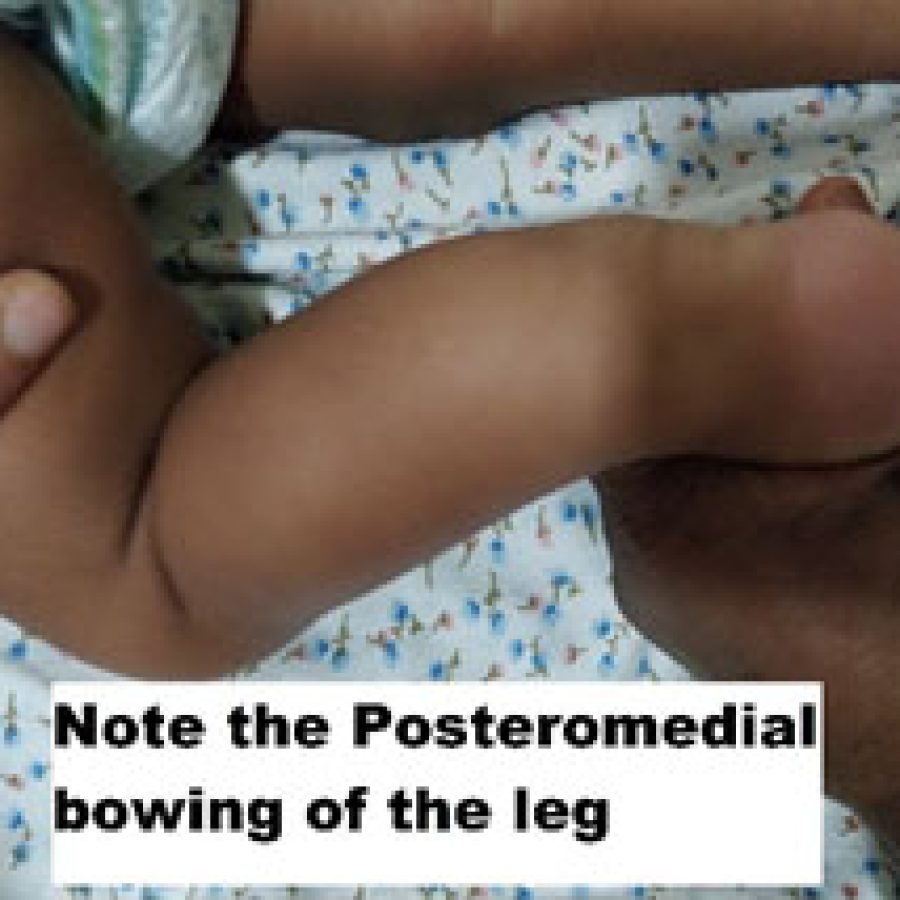

CONGENITAL POSTEROMEDIAL BOWING

Posteromedial bowing is a benign clinical condition with a good natural history. It is mostly due to the intrauterine positioning of the leg. It is most often associated with calcaneovalgus foot. It spontaneously corrects by the age of 5-7 years. If there is more than 3-4 cm of shortening, then surgical intervention is necessary to equalize the limb length.

Most often than not, this should not be confused with anterolateral bowing of the leg, which is almost always pathological. Anterolateral bowing is mostly because of congenital pseudarthrosis of the tibia. Congenital Pseudarthrosis of tibia and fibula is one of the most challenging surgical problems in pediatric orthopedic surgery, and it is important to distinguish from benign posteromedial bowing of the tibia.

When to Refer

It is important to refer all bowing of the leg to the pediatric orthopedic surgeon as sometimes it is difficult to differentiate the two disorders. If one is very sure about the Posteromedial bowing of the leg, then one can wait for 2-3 years with reassurance to the family